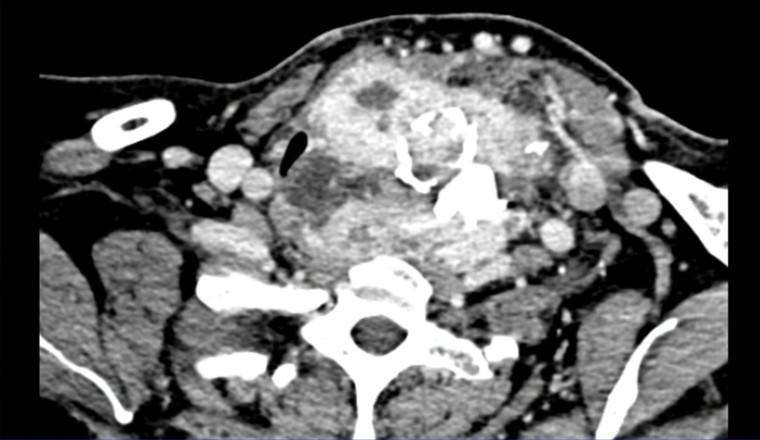

Giữa tháng 5/2019, bệnh nhân đến khám tại khoa Ung bướu - Bệnh viện quận Thủ Đức. Qua xét nghiệm, bác sĩ Nguyễn Triệu Vũ, Trưởng khoa Ung bướu nhận định đây là trường hợp bướu giáp tái phát, khối u lớn gây đè dẹp khí quản, dính các mạch máu xung quanh, thòng sâu vào lồng ngực đồng thời bệnh nhân còn bệnh cao huyết áp và tiểu đường kèm theo.

Ca mổ được tiến hành khá suôn sẻ, mặc dù khối u nhiều năm đã bị chai cứng và xơ dính vào các thần kinh, mạch máu, thực quản… nhưng bác sĩ đã nhẹ nhàng bóc tách cắt trọn toàn bộ mô tuyến giáp và u, bảo vệ an toàn các cấu trúc quan trọng, ngăn không cho khối bướu tái phát. Toàn bộ khối u lớn 9x 18cm và cân nặng khoảng 1,1kg đã được bóc tách thành công.

Khối bướu cổ khổng lồ được bóc tách thành công - Ảnh: Bảo vệ Pháp luật